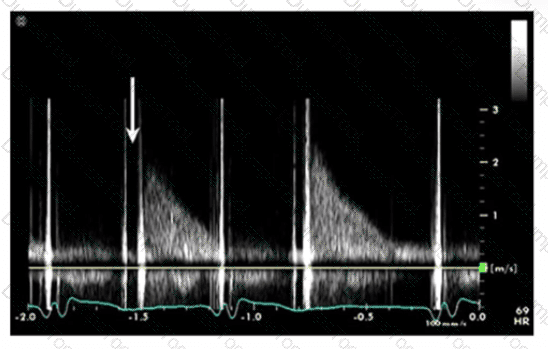

Which valve and secondary finding are associated with the 'flying W sign on spectral Doppler and M-mode?